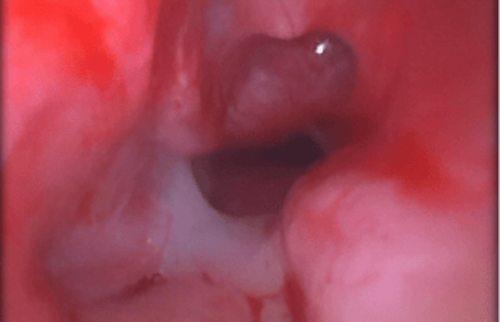

Darstellung einer raumfordernden Gewebezubildung (Tumor oder Polyp), die den Atem- oder Speiseweg stark einengt.

Endoskopische Ansicht einer knotigen Schleimhautveränderung (z. B. Polyp oder kleiner Tumor).